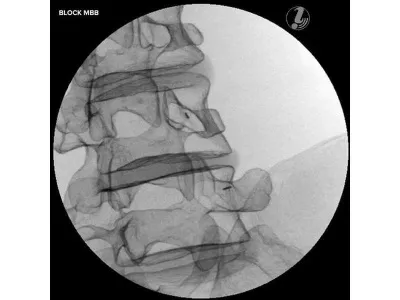

Тренажер для спинальных инъекций с визуальным контролем

Тренажер для инъекций в поясничный отдел с визуальным контролем позволяет повысить процент успешных результатов при медицинском вмешательстве на позвоночнике путем использования стандартизированного обучения выполнению инъекций.

- Блокада фасеточных суставов

- Блокада медиальной ветви (MBB/RF)